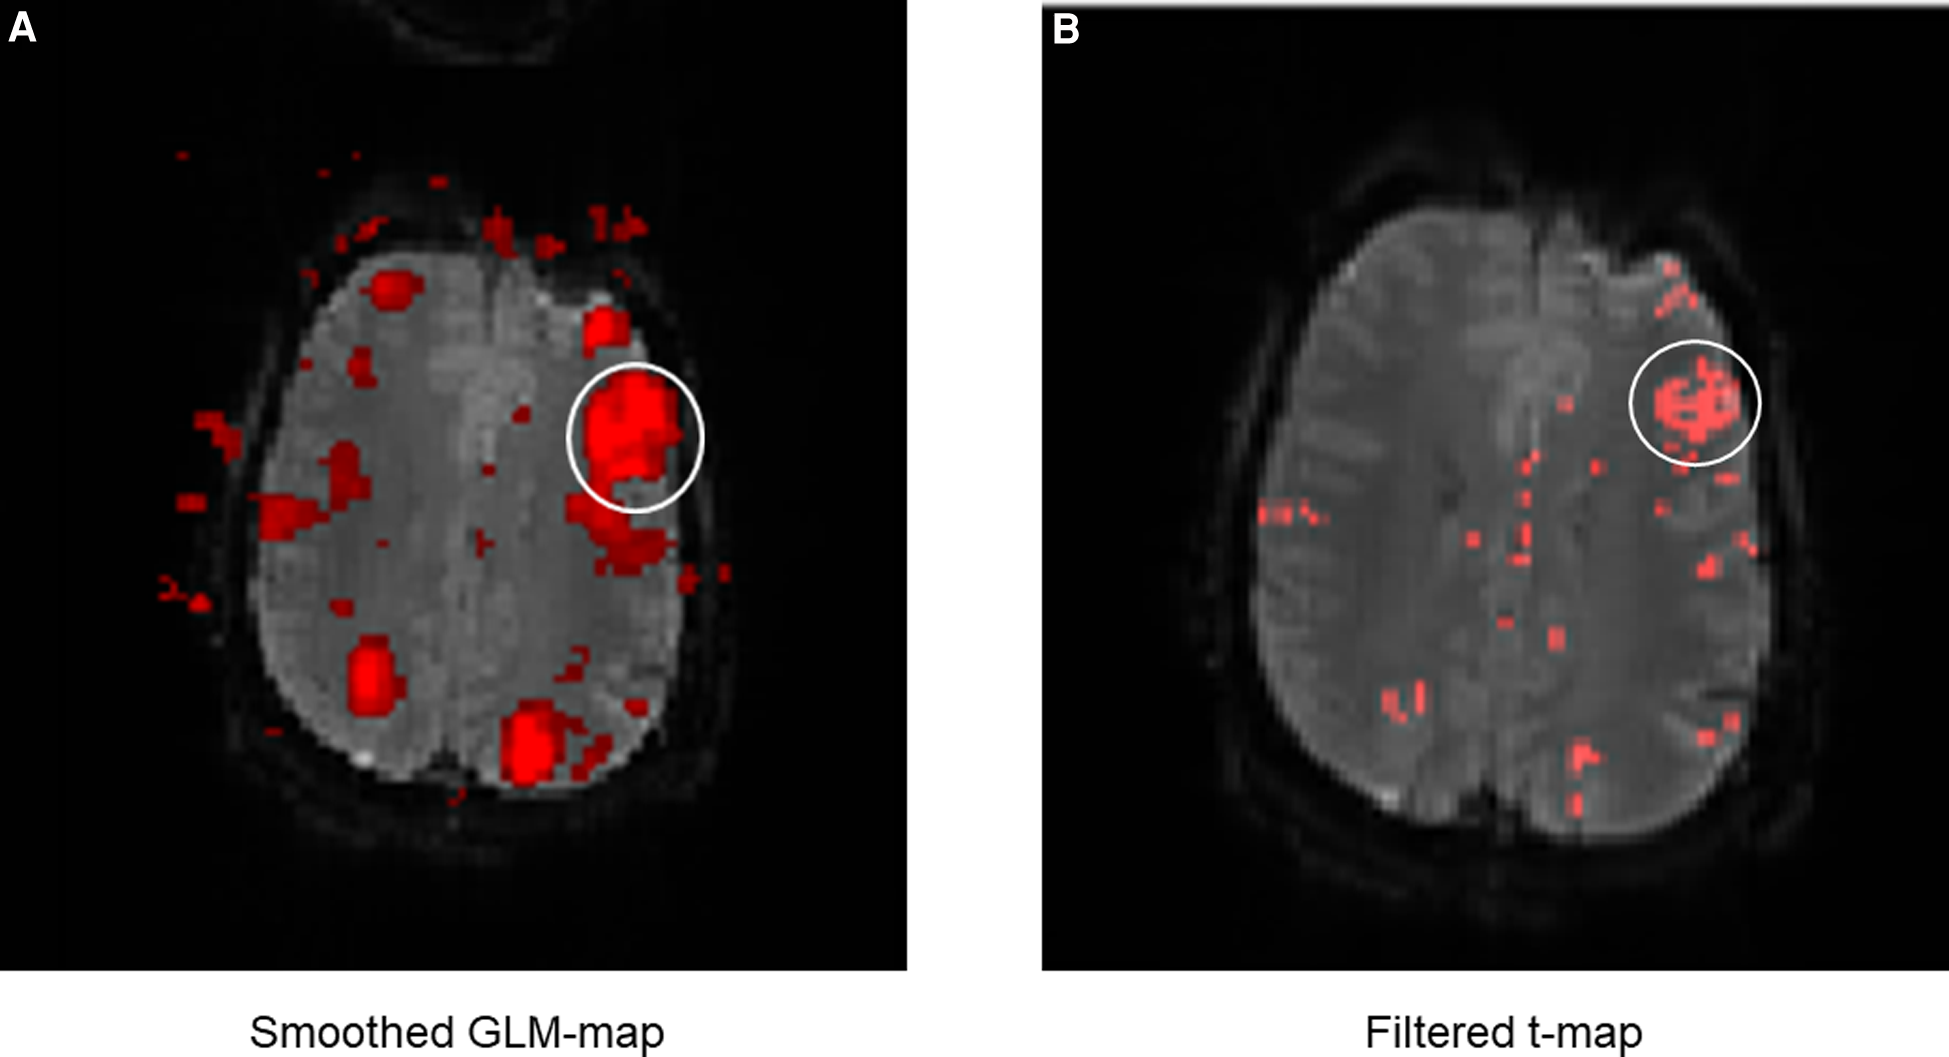

The next part of the evaluation focused on the display and readability of the language activations. For the comparison of both methods, the display of language activations was evaluated depending on the presence of directly adjacent activations (Figure 8).

FIGURE 8

www.frontiersin.org

Figure 8. Exemplary comparison of the display of LAs between the GLM map (A) and the filter t-map (B). The white circle marks Broca's area. It can be noticed that the display of Broca's area is displayed much larger on the GLM map than on the filter t-map, even though the same fMRI data were used. This is mainly due to the smoothing of the GLM maps, causing surrounding activations to merge into the language activations (in this case of Broca's area). This can lead to differences between the displayed and truly measured spatial boundaries of the LAs. The presence of directly adjacent and merging activations complicates the evaluation and the exact localization of the LAs and was incorporated as a negative aspect in the evaluation of the activation maps. The display of Broca's area on the filter t-map (B) in comparison is smaller, distinguishable from sur-rounding activations and shows only the truly measured activations and spatial boundaries of activations.

The results (Table 3) showed that activations directly adjacent to the language activations were displayed less frequently on filter t-maps than on GLM maps. Especially with the fMRI data of the subjects, which were mostly of high quality, the LAs could be displayed more clearly by using the filter t-map. When displaying Broca's area, only eight directly adjacent activations were found on the filter t-maps, while the GLM maps showed 13 directly adjacent activations. In a direct map-to-map comparison, the filter t-map displayed Broca's area better on 6 maps, while the GLM map was superior in only one case. On six maps, both methods showed directly adjacent activations to the LAs.